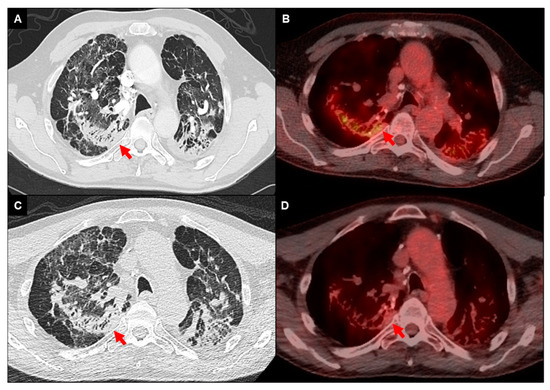

- Regis, C.; Benali, K.; Rouzet, F. Fdg pet/ct imaging of sarcoidosis. Semin. Nucl. Med. 2023, 53, 258–272. [Google Scholar] [CrossRef]

- Keijsers, R.G.; Grutters, J.C.; Thomeer, M.; Bois, R.M.D.; Van Buul, M.M.; Lavalaye, J.; Van Den Bosch, J.M.; Verzijlbergen, F.J. Imaging the inflammatory activity of sarcoidosis: Sensitivity and inter observer agreement of 67ga imaging and 18f-fdg pet. Q. J. Nucl. Med. Mol. Imaging 2011, 55, 66–71. [Google Scholar]

- Braun, J.J.; Kessler, R.; Constantinesco, A.; Imperiale, A. 18f-fdg pet/ct in sarcoidosis management: Review and report of 20 cases. Eur. J. Nucl. Med. Mol. Imaging 2008, 35, 1537–1543. [Google Scholar] [CrossRef]

- Vender, R.J.; Aldahham, H.; Gupta, R. The role of pet in the management of sarcoidosis. Curr. Opin. Pulm. Med. 2022, 28, 485–491. [Google Scholar] [CrossRef] [PubMed]

- Mostard, R.L.; Verschakelen, J.A.; van Kroonenburgh, M.J.; Nelemans, P.J.; Wijnen, P.A.; Voo, S.; Drent, M. Severity of pulmonary involvement and 18f-fdg pet activity in sarcoidosis. Respir. Med. 2013, 107, 439–447. [Google Scholar] [CrossRef] [PubMed]

- Ambrosini, V.; Zompatori, M.; Fasano, L.; Nanni, C.; Nava, S.; Rubello, D.; Fanti, S. 18f-fdg pet/ct for the assessment of disease extension and activity in patients with sarcoidosis: Results of a preliminary prospective study. Clin. Nucl. Med. 2013, 38, e171–e177. [Google Scholar] [CrossRef] [PubMed]

- Chen, H.; Jin, R.; Wang, Y.; Li, L.; Li, K.; He, Y. The utility of 18f-fdg pet/ct for monitoring response and predicting prognosis after glucocorticoids therapy for sarcoidosis. BioMed Res. Int. 2018, 2018, 1823710. [Google Scholar] [CrossRef] [PubMed]

- Maturu, V.N.; Rayamajhi, S.J.; Agarwal, R.; Aggarwal, A.N.; Gupta, D.; Mittal, B.R. Role of serial f-18 fdg pet/ct scans in assessing treatment response and predicting relapses in patients with symptomatic sarcoidosis. Sarcoidosis Vasc. Diffuse Lung Dis. 2016, 33, 372–380. [Google Scholar] [PubMed]